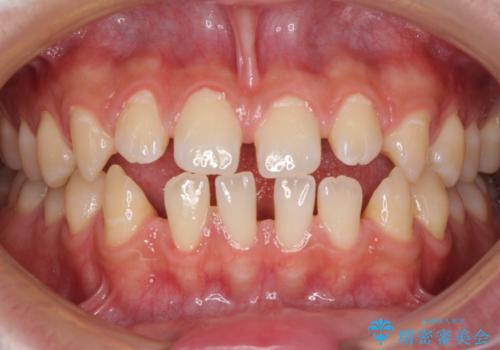

空隙歯列を閉じる 舌のトレーニングとワイヤー矯正

- 上下前歯の隙間を気にして来院された患者様です。

飲み込みや話をするときに舌を突出させる癖が強くあり、それが原因でスペースが空いていました。

舌癖を改善するためのトレーニングを行いながら、ワイヤー装置を用いて前歯の隙間を閉じていくこととしました。